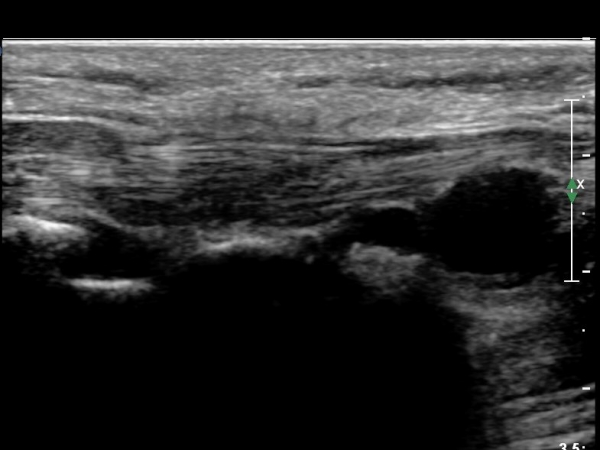

¾à 2ÁÖÀüºÎÅÍ  ¾öÁö¿Í °ËÁö »çÀÌÀÇ ±ÙÀ°ÀÌ À§ÃøµÇ°í ¼Õ°¡¶ô ÈûÀÌ ¾àÇØÁü.